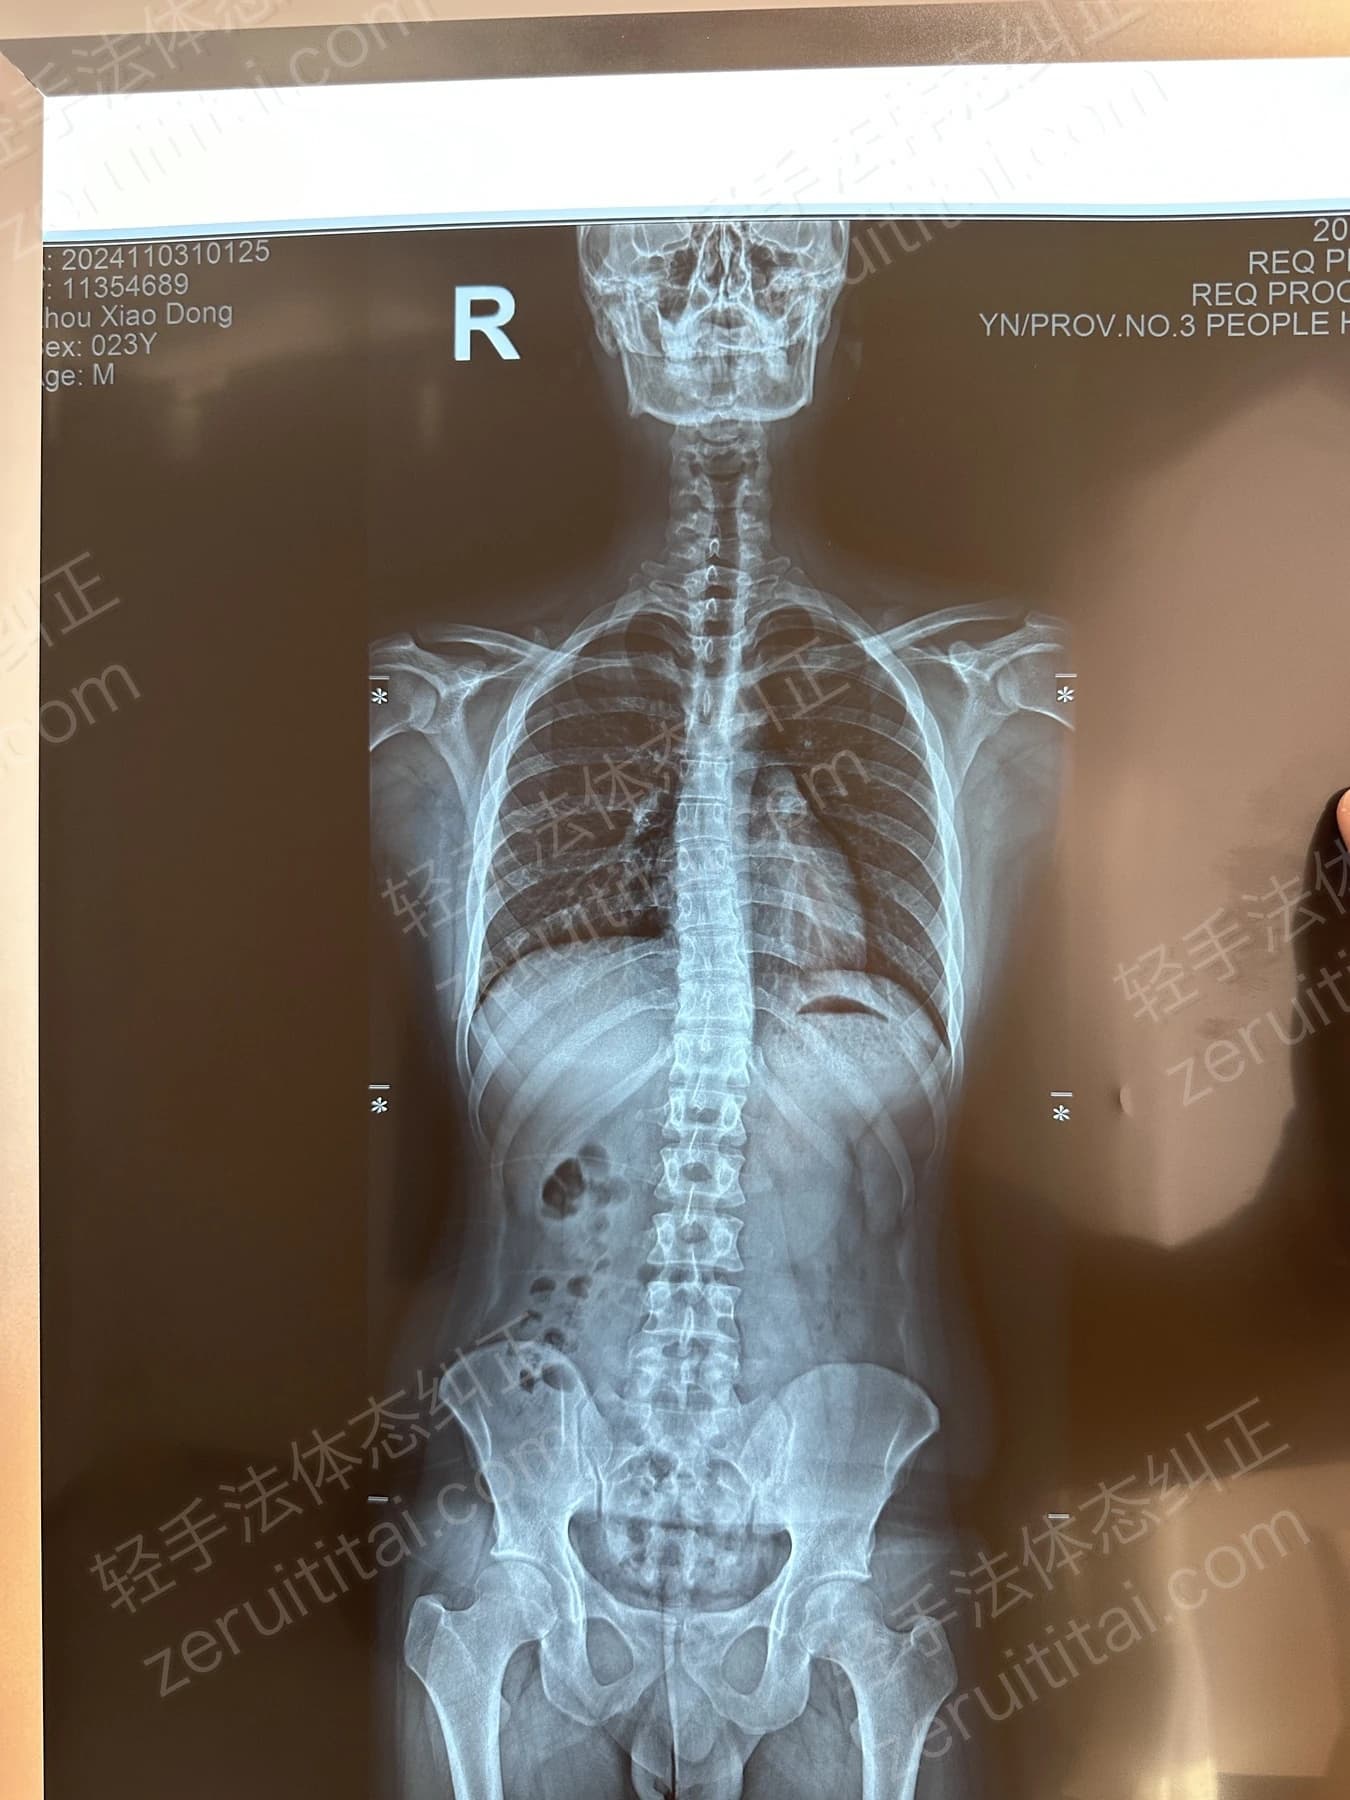

2022.06.27

第 1 次记录